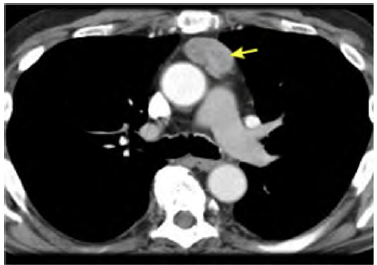

Uma paciente de 47 anos de idade, com sintomas gripais agudos, realizou exames de imagem de tórax por suspeita de Covid-19. A hipótese não se confirmou, porém uma tomografia computadorizada de tórax, representada pela imagem a seguir, evidenciou uma massa heterogênea de contornos bem definidos em topografia de mediastino anterior, em localização de timo, de aproximadamente 4,5 cm x 2,9 cm. Não apresentava linfonodos aumentados no exame de imagem. Realizaram-se, ainda, tomografias computadorizadas de encéfalo e de abdome, que não mostraram alterações.